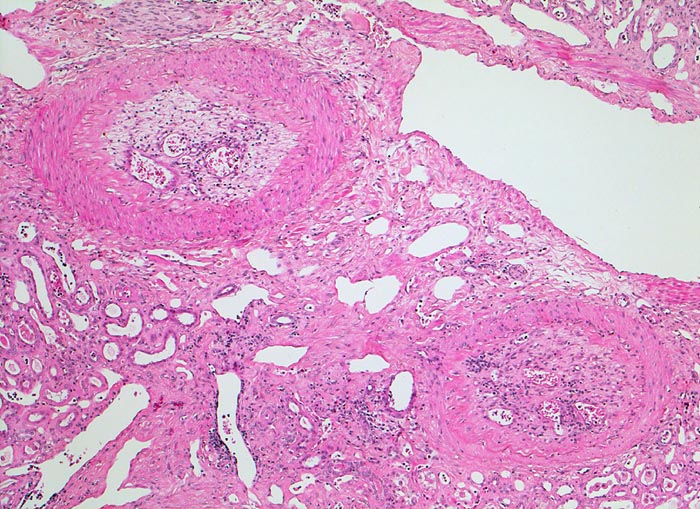

alter rekanalisierter Gefässverschluss

Diese intrarenalen Arterienäste weisen alte organisierte und durch kapilläre Gefässe rekanalisierte embolische Verschlüsse auf.

Chronisches Vorhofflimmern mit Morbus embolicus: anämische Infarkte verschiedenen Alters in beiden Nieren und in der Milz. Alte abgebaute Enzephalomalazie im Versorgungsbereich der Arteria cerebri media rechts.

Die meisten Arterienverschlüsse in der Niere sind embolisch bedingt. Die Niere ist wegen ihrer starken Durchblutung oft von Embolien betroffen. Da die Niere durch Endarterien versorgt wird, handelt es sich um anämische Infarkte. Thrombotische Verschlüsse bei fortgeschrittener Atherosklerose (Diabetes mellitus) oder im Rahmen einer Vaskulitis sind selten.